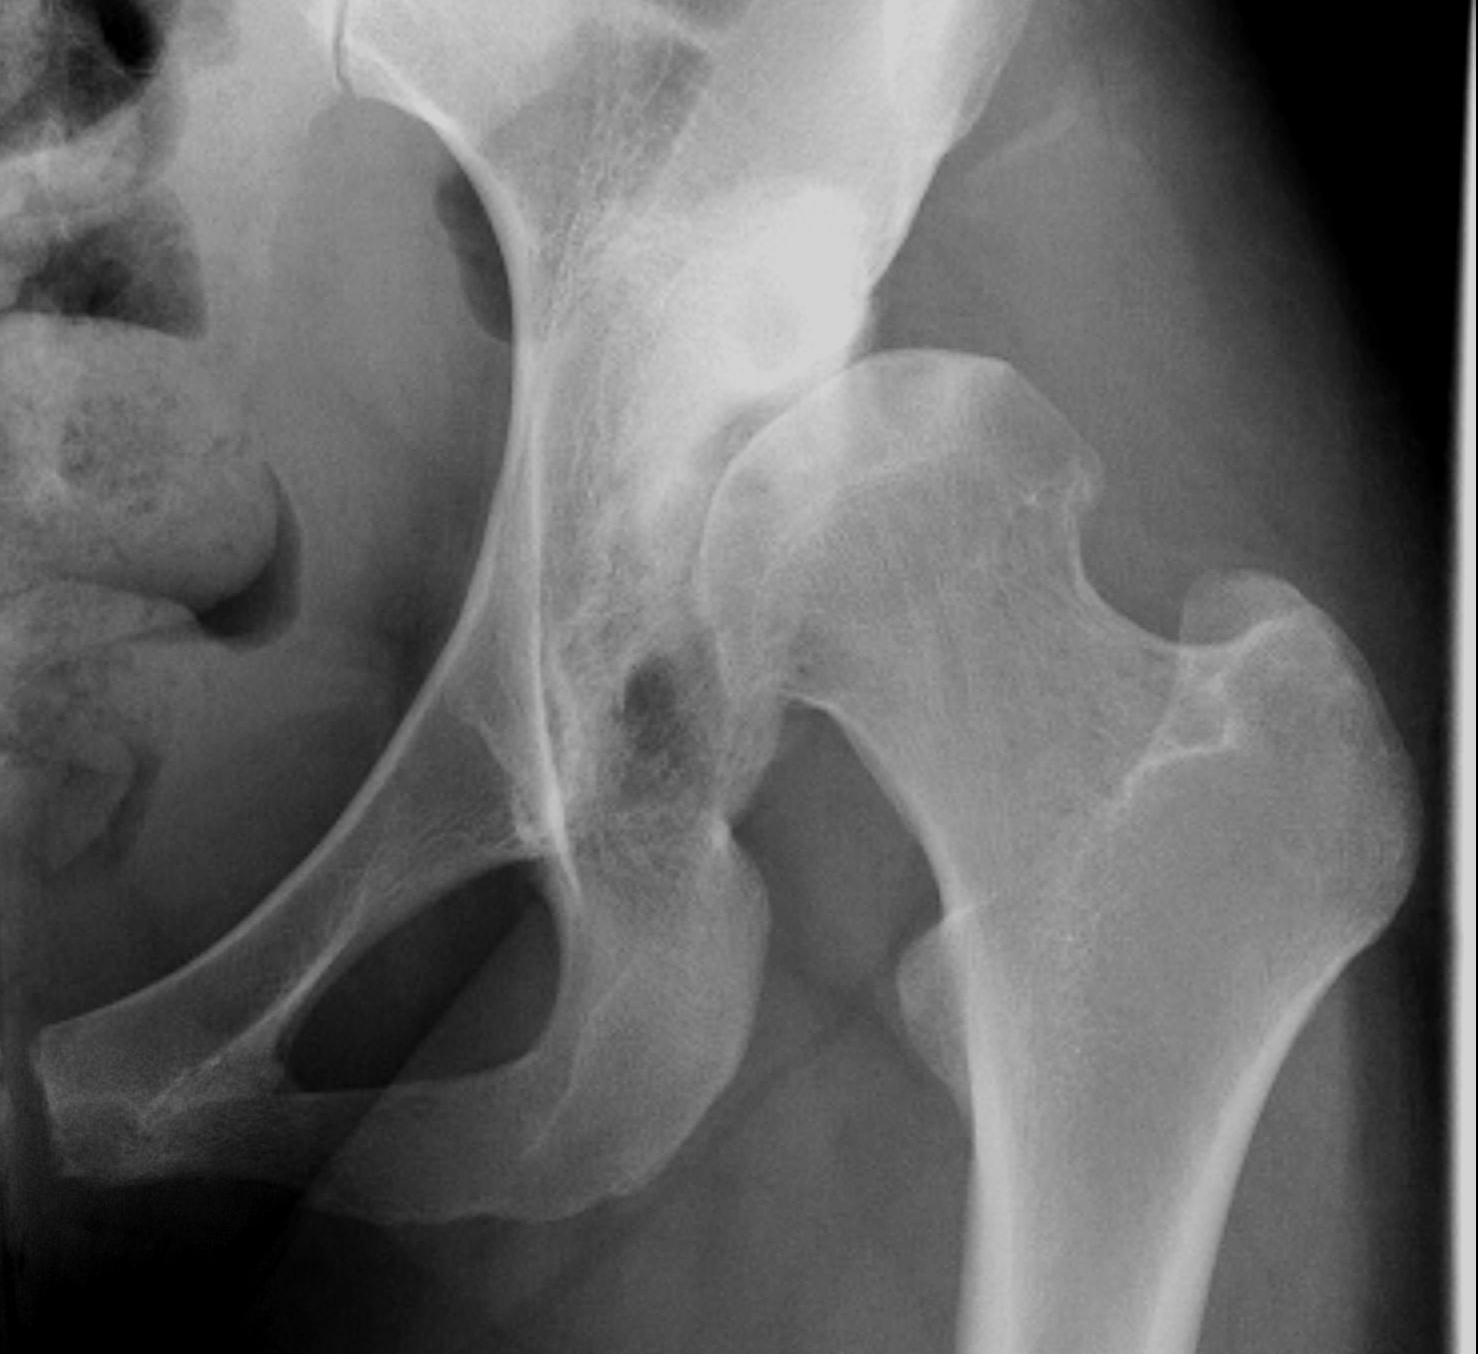

Crowe I